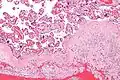

Micrograph of decidualized endometrium due to exogenous progesterone. H&E stain.

The decidua has a histologically-distinct appearance, displaying large polygonal decidual cells in the stroma. These are enlarged endometrial stromal cells, which resemble epithelium (and are referred to as "epithelioid").

Decidualization includes the process of differentiation of the spindle-shape stromal fibroblasts into the plump secretory decidual cells, which create a pericellular extracellular matrix rich in fibronectin and laminin (similar to epithelial cells).